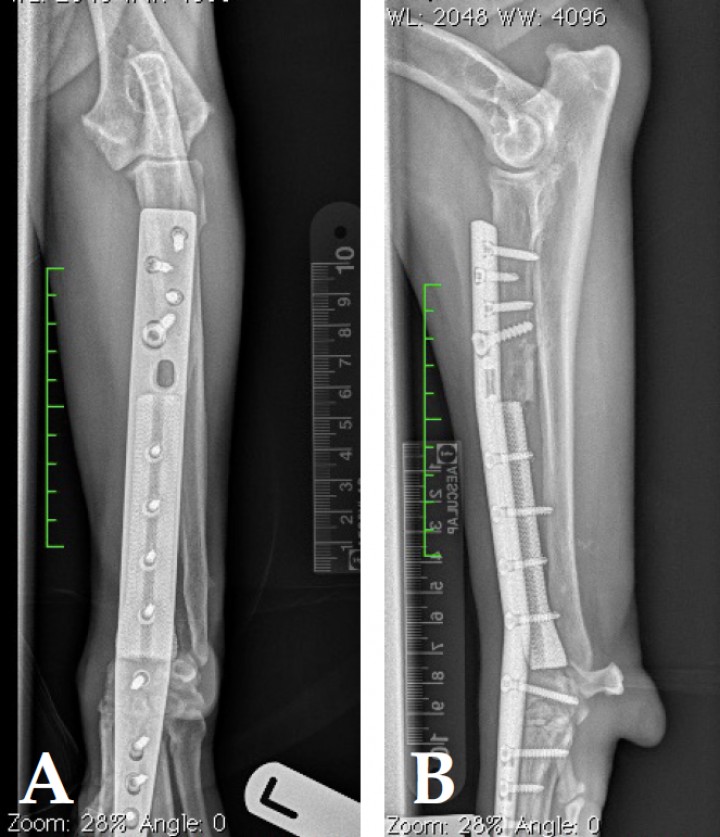

<p>Radiografías cráneo-caudal (A) y lateral (B) tras la realización de cirugía con preservación del miembro mediante la técnica de endoprótesis.</p>

Figura 8

Radiografías cráneo-caudal (A) y lateral (B) tras la realización de cirugía con preservación del miembro mediante la técnica de endoprótesis.